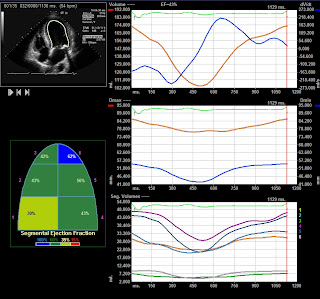

Eco 3D e a (falta de ) visão do cirurgião

Fem. 30 a. histórico de patologia congênita e troca da valva aórtica por mecânica e plastia da valva mitral. Mas o cirurgião cardíaco insiste que a insuficiência mitral é cirúrgica e quer um transesofágico!(?).

E depois dizem que o 3D dá a visão do cirurgião!!!!